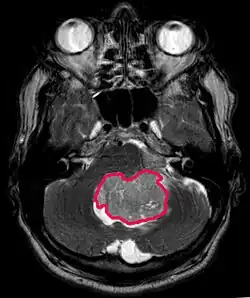

Le médulloblastome est la tumeur cérébrale maligne la plus fréquente chez l'enfant. L'incidence la plus élevée survient chez les enfants âgés de 2 à 7 ans. Le plus grand risque de maladie demeure dans l'enfance, car le médulloblastome est très rare chez les personnes de plus de 21 ans.

Cette tumeur est typique de la fosse postérieure, où elle est localisée dans les deux hémisphères du cervelet ou dans le vermis cérébelleux. Parce qu'il est envahissant et à croissance rapide, il se propage généralement à d'autres parties du système nerveux central (SNC) via le LCR et peut infiltrer le plancher du quatrième ventricule voisin et les méninges. Plus rarement, des métastases supplémentaires du SNC peuvent survenir. Lorsque la tumeur maligne survient, les symptômes comprennent la perte d'équilibre, l'incoordination, la diplopie, la dysarthrie et l'atteinte du quatrième ventricule, ce qui entraîne souvent une hydrocéphalie obstructive, des maux de tête, des nausées et des vomissements et une démarche instable.

L'IRM montre généralement une lésion de contraste massive impliquant le cervelet. Comme mentionné ci-dessus, le médulloblastome a une forte propension à infiltrer localement les leptoméninges ainsi qu'à se propager à travers l'espace sous-arachnoïdien, impliquant les ventricules, la convexité cérébrale et les surfaces leptoméningées de la colonne vertébrale. Par conséquent, il est nécessaire de mettre en résonance tout l'axe crânio-spinal.

Le but de la chirurgie est d'enlever autant que possible la masse présentée par la lésion. En effet, les tumeurs résiduelles postopératoires entraînent un moins bon pronostic. La présence de cellules tumorales dans le liquide céphalo-rachidien ou la détection par résonance de métastases leptoméningées est également un signe avant-coureur d'un pronostic défavorable. La chirurgie seule n'est généralement pas curative. Dans certains cas, cependant, une irradiation thérapeutique de l'axe craniospinal, focalisée sur le site tumoral primaire, peut en résulter. L'ajout d'une chimiothérapie après la radiothérapie augmente le taux de guérison. Des médicaments à base de platine (cisplatine ou carboplatine), de l'étoposide et un agent alkylant (cyclophosphamide ou lomustine) sont utilisés avec la vincristine. Avec un traitement approprié, les cas de longue survie de plus de 3 ans chez les patients atteints de médulloblastome varient de 60 à 60 ans et 80 Pour cent.